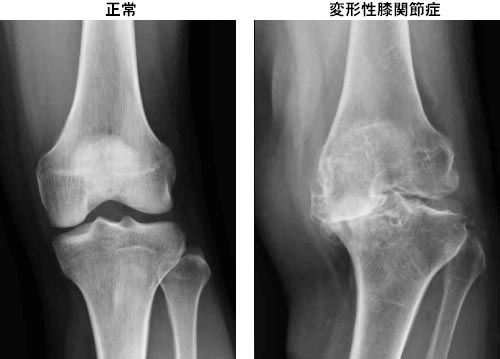

このように膝に雑巾絞りのようなストレスが掛かり続けると、軟骨同士がぶつかり合い「変形性膝関節症」となるのです。